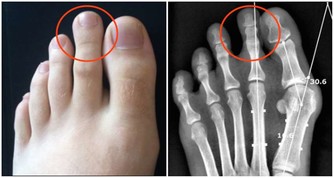

核心提示: 久坐,已經成為現代人的生活狀態。然而,它也被認為是離死亡最近的方式。 上班時間都坐在座位上,回到家裡要麼坐在沙發上看電視,要麼坐著玩電腦。久坐,已經成為現代人的生活狀態。然而,它也被認為是離死亡最近的方式。久坐的各種危害,你瞭解嗎? 1.會致血液循環不良: 久坐不動會使靜脈回流受阻,直腸肛管靜脈出現擴張,血液瘀積,導致靜脈曲張而出現痔瘡。